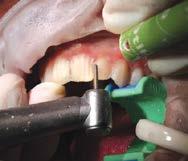

Ridgfield Park, N.J.) o TuffTemp™ Plus (PULPDENT; Watertown, Mass.), rellené la matriz putty y cemento sobre las piezas 22-12 sin preparar. Removí el exceso de acrílico mientras el material se asentaba en la boca del paciente para reducir el tiempo que hubiera necesitado para limpiar el acrílico endurecido (Figura 5).

La matriz fue removida después de que el material del mockup se asen tó. Se pueden realizar pequeños ajus tes en este punto de ser necesario. El mockup intraoral nos dio la oportu nidad, tanto a mí como a mi pacien te, de revisar la estética, fonética y el funcionamiento general del diseño (Figura 6).